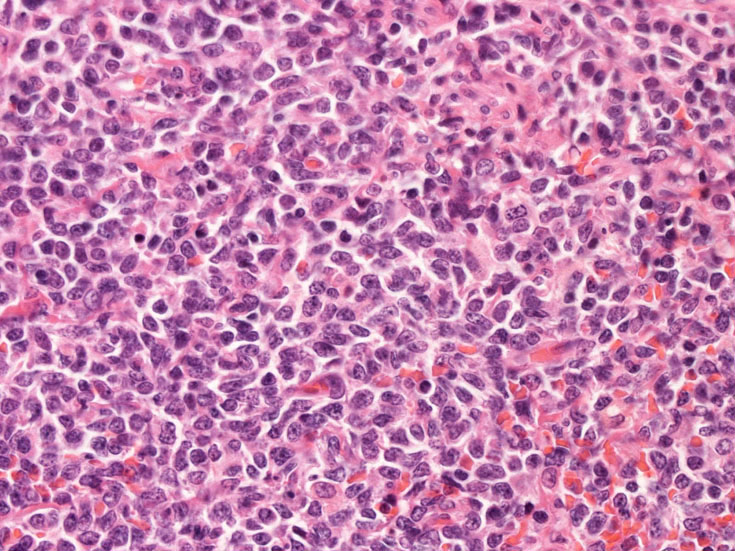

真皮, 毛嚢周囲, 皮下組織にびまん性または結節様に異型細胞の浸潤増殖が認められる(Fig.07)。表皮への浸潤は認められない(Fig.08)。真皮上層への浸潤細胞は類円形,多角形のhyperchromatic nucleiをもつ。細胞質は明るくclearに見える(Fig.09)。毛嚢周囲に浸潤する細胞はリンパ節への浸潤細胞と同様の形態を示す(Fig.10, 11). 腫瘍細胞はCD123陽性を示した(Fig.12)

skin_03.jpg

skin_04.jpg

Fig.10Fig.11Fig.12